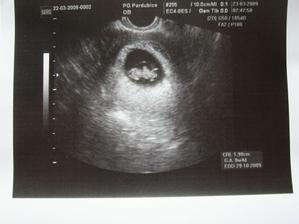

Nová naděje. Bohužel to bylo opět stejné, jako již dvakrát předtím. Třetí revize, třetí ztráta naděje. Jsem po laparoskopii a hysteroskopii a čekáme na výsledky imunologie v Plzni. Pak se uvidí co dál. V únoru 2009 nám v Sanusu doporučili ještě dva měsíce domácího snažení. Tak jsme se snažili a nyní napjatě sledujeme čárku. HCG nám krásně stoupá, 20. den po ovulaci je 2066. Máme 1. fotku dutinky. Přes nejrůznější potíže a patnáctidenní hospitalizaci nám miminko krásně roste. 22. dubna konečně po čtrnácti dnech ukázalo nosánek, máme nosní kůstku, NT je 2,0. Máme vše, co máme mít a rodiče se dnes poprvé společně dívali na ultrazvuk. Viděli mě i 4D, to koukali. Odnesli si video a teď na něj pořád koukají. Další kontrola náš čeká 5. května, opět ultrazvuk, triple testy a poradna. Trošku změna situace, mamka se mnou leží od 27. dubna v nemocnici, ale já ji dělám radost, rostu, 16.6. už vážím 360 gramů a od 5.6. ji kopu a ona o tom ví. Od 10. 6. se nám začal malinko měnit nález až jsme museli 10. 7., gr. h. 24+2 na cerclage, potom jsme měli zánět ledvin a astmatický záchvat. Pořád mamce tvrdlo břicho, tak se bez infuzí neobejde. 18. 7. se ještě objevilo krvácení, ale nebylo to nic závažného, byli jsme na ultrazvuku a vážím 908 gramů. V pátek 24.7. se to zlepšilo a kapeme na nejnižší rychlost, hurá. Mamka zatím nesmí chodit, má to slíbeno na 2. září. Kapeme sice na nejvyšší rychlosti, ale na ultrazvuku 4.8. mám odhad 1280 gramů. Dne 18.8. jsme byli na ultrazvuku a mám odhad 1750 gramů, mám trochu víc plodové vody a tak si tam plavu jako v bazénku. Dne 28.8. jsme byli s mamkou zase na ultrazvuku, vážím už 1950 gramů, mám udělaný krásný 3D fotečky, vody už nemám tolik moc, tak je mamka ráda. Jen se nám zase zkrátil čípek, už mě tam drží jen steh a 13 mm, ale držím mamce pěstičky, aby jsme vydrželi. No a taky si musím zvykat, mamka totiž má už dovoleno chodit na wc, a já jsem byl zvyklej, že pořád leží. Je sice z toho unavená, ale šťastná. Já jsem jí ještě udělal radost, že jsem se přetočil hlavičkou dolů. Dne 1.9. se mi konečně podařilo zbavit se té nitě, co tam mamka měla. Všichni jsou překvapení, jak se to mohlo stát, ale steh je pryč. Dne 10. 9. jsme s mamkou byli zase na ultrazvuku, vážím 2368 gramů (33+1). Hrdlo máme sice jen 9 mm, ale já se tam ještě udržím! Plodové vody mám už akorát, mamce klesly jaterní testy, žlučové kyseliny jsou v normě, tak má radost. Tak dnes 17. 9. jsem se byl zase vážit, mám 2517 gramů. Hrdlo má mamka jen 6,7 mm s obrovitým funnelingem, ale pořád drží. Denně mi točí monitory, mám je vzorné a pořád nemůžu přijít na to, jak ty sondy odkopnout. 26.9. pustil pan doktor mamku na propustku, byla poprvé 12 hodin mimo nemocnici, byli jsme na zahradě, grilovali jsme a já jsem babičce, dědečkovi a strejdovi předváděl, jak umím krásně kopat. Mamka byla moc šťastná. Večer se vrátila do nemocnice, dala si po 23. hodině sprchu a když usínala, tak jsem ji hodně překvapil, vypustil jsem svůj bazén. A tak se nešlo spinkat, ale na porodní sál. Šlo to pěkně a přesně ve 4.00 hodin jsem se narodil za skvělé asistence mého tatínka, který mamince na sále moc pomáhal. Vážím 2740 gramů a měřím 50 cm. Dosáhl jsem gestačního stáří 35+4. Rodiče a velká spousta lidí kolem ze mě mají velikánskou radost. Trošku jsem odmítal v inkubátoru dýchat, tak mě 1 den pomáhal CPAP. Večer mi ho vzali a teď už se snažím sám. mamka za mnou chodí a já jsem rád, když ji vídím. Dnes jsem na ni poprvé otevřel očička, snažím se papat, dnes už ze stříkačky. Tatínek je ze mě unešenej a já jsem rád, když mě přijde pohladit a vyfotit.